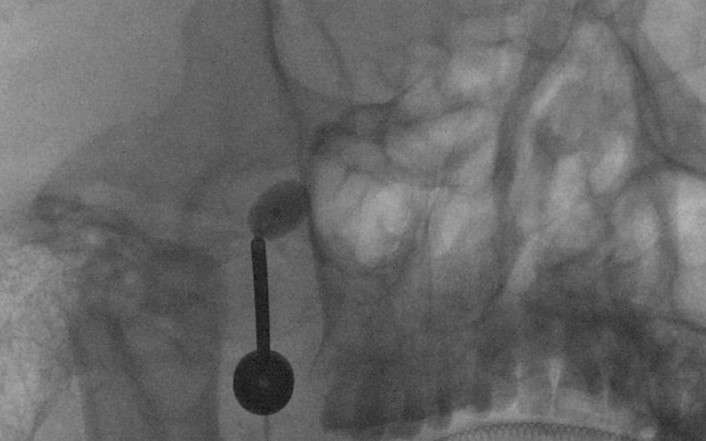

三叉神經(jīng)痛往往疼痛劇烈,且反復(fù)發(fā)作,被稱為‘’天下第一痛‘’。 疼痛發(fā)生后患者首先采取藥物治療,如卡馬西平及中藥等,一般可起到緩解疼痛的作用。但時(shí)間久了,一部分患者出現(xiàn)藥物沒(méi)效果了,或出現(xiàn)比較重的藥物不良反應(yīng),這種情況就要采取外科手術(shù)一類的方法。 這些方法主要包括顯微血管減壓術(shù)、射頻熱凝術(shù)、球囊壓迫術(shù)。那么采取哪種方法最為合適呢?除了這幾種方法的具體特點(diǎn)外,還要結(jié)合患者的身體狀況、年齡、治療經(jīng)過(guò)等因素來(lái)考慮。 顯微血管減壓術(shù)從發(fā)病機(jī)理來(lái)講,可以通過(guò)顯微手術(shù)解除疼痛的根本原因,而且一般不會(huì)影響面部的感覺(jué),因此被認(rèn)為是首選的外科治療方法,多數(shù)情況下可以選擇。 但如果患者是年齡很大,身體比較衰弱,或者是已經(jīng)接受過(guò)血管減壓術(shù)或其他治療復(fù)發(fā)的,則可能選擇創(chuàng)傷更小的方法更為合適,球囊壓迫術(shù)對(duì)此種情況尤為合適。球囊壓迫術(shù)是僅進(jìn)行一次性穿刺就可完成的微創(chuàng)治療方法,具體做法是采取全麻,治療期間患者不會(huì)有疼痛感覺(jué),在口角旁邊扎入穿刺針,在DSA或CT等機(jī)器的引導(dǎo)定位下精準(zhǔn)到達(dá)三叉神經(jīng)半月節(jié),再導(dǎo)入球囊壓迫一到兩分鐘就可完成這個(gè)手術(shù)。 球囊壓迫術(shù)的止痛效果可以達(dá)到90%左右,患者的恢復(fù)很快,一般術(shù)后第二天就可出院了。和其他方法一樣,雖然也存在著一定程度復(fù)發(fā)的問(wèn)題,但其具有微創(chuàng)、治療期間無(wú)痛苦、起效快、恢復(fù)快、可重復(fù)等優(yōu)點(diǎn),不失為治療三叉神經(jīng)痛的一種較好方法。